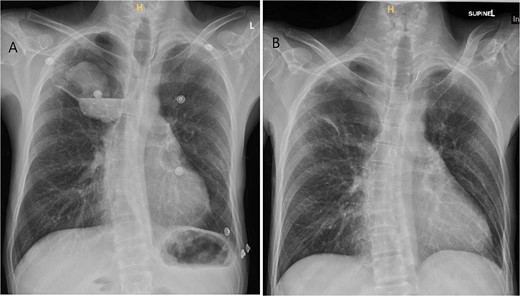

A 36-year-old male was referred to the Thoracic Surgery Service due to an incidental finding of a 5-cm soft tissue density within a known long-standing large right apical bulla on a chest X-ray (Fig. 1A). This lesion was new compared to the patient’s last chest X-ray 5 months prior (Fig. 1B). A computed tomography (CT) scan of the chest, abdomen, and pelvis demonstrated a 4.4 × 5.2 cm intracavitary solid-appearing mass within the wall of the longstanding bulla, along with heterogeneous fluid layering within the cavity with questionable enhancement (Fig. 2). This was reported as concerning for a primary bronchogenic malignancy (versus adherent fungus ball) with a superimposed infection. The patient had no respiratory or constitutional symptoms.

Chest X-ray imaging of incidentally found right new apical lung mass (A). This lesion was absent in the patient’s X-ray taken 5 months prior (B).